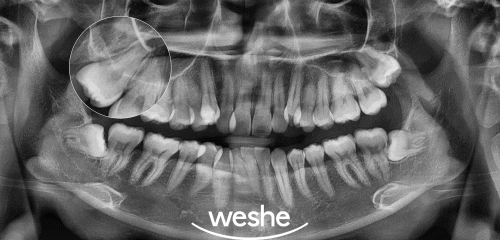

마곡역 수면치과 에서 준비한 엑스레이를 보면

위아래 좌우 총 4개의 제3대구치가 있는 것을

관찰할 수 있습니다.

이 중 좌우 아랫니는 누워서 자라고 있어

주위 인접치를 밀어내어 악영향을 주고 있으며,

음식 찌꺼기로 인해 세균이 번식하여

염증과 부기를 유발 시키고 있습니다.

오른쪽 윗니의 경우

주위 연조직을 지속적으로 깨물게 되어

상처와 부기가 생기고 있는 것으로 확인됩니다.

이러한 점을 보아

왼쪽 위를 제외한 사랑니 발치 를

우선으로 진행하는 것이 좋다 판단됩니다.